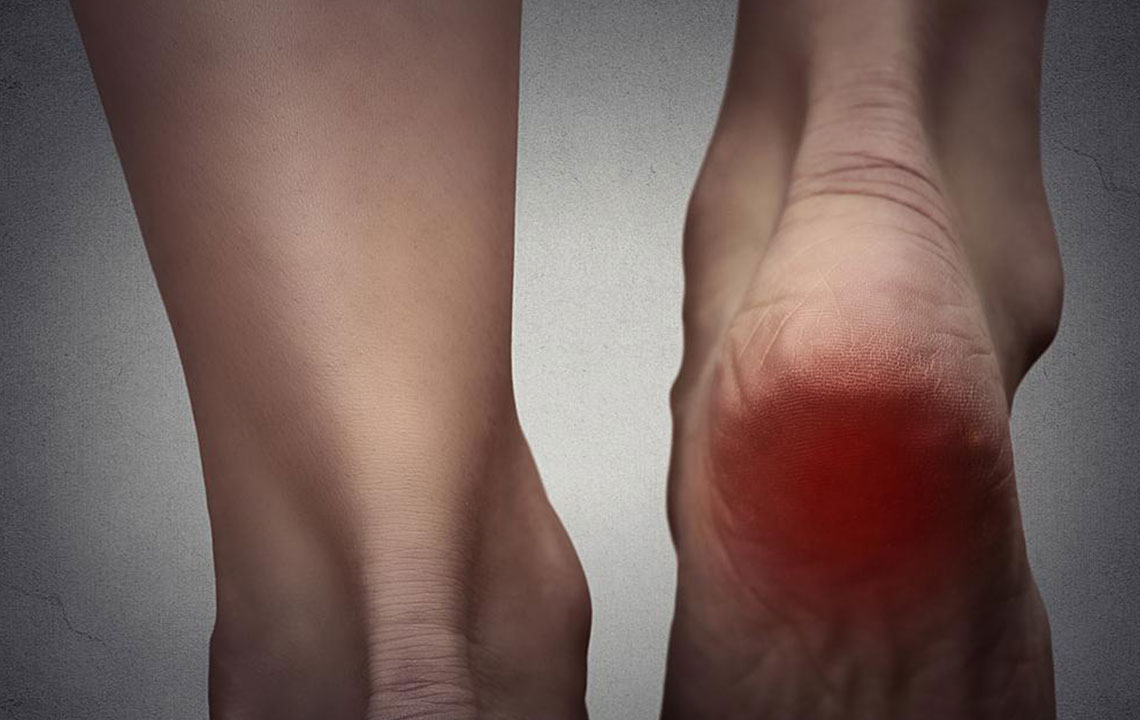

Among the more common ailments prevalent today, the issue of burning foot pain ranks high on the list. However, most sufferers remain blissfully ignorant that this could be a cause for concern. Burning foot pain could arise from some nerve damage. Such nerve damage occurs in the leg and is medically referred to as neuropathy. There are many reasons besides this that could be a cause for such burning sensation. More often than not though, diabetes comes across as the culprit. The prime idea behind all treatments for such pain is related to controlling nerve damage as well as pain reduction.

Neuropathy occurs when the damaged fibers of nerves misfire or become overactive. These nerves signal the sensation of pain to the brain. Therefore, despite the absence of a cut or a wound, the sensation of pain occurs. Nerves in the leg tend to get affected first, in patients with neuropathy. There could be accompanying numbness or tingly sensations along with burning foot pain. Burning pain in the foot could also be accompanied by excess sensitivity to touch on the foot area. The pain could be intense or mild from time to time.

There could be infections on the feet or even inflammations that could lead to burning pain in the feet. Athlete’s foot is a very common fungal infection that causes such pain. Moreover, in case the blood circulation in your legs is poor, you may experience burning feet, pain, and tingling especially when you walk around.